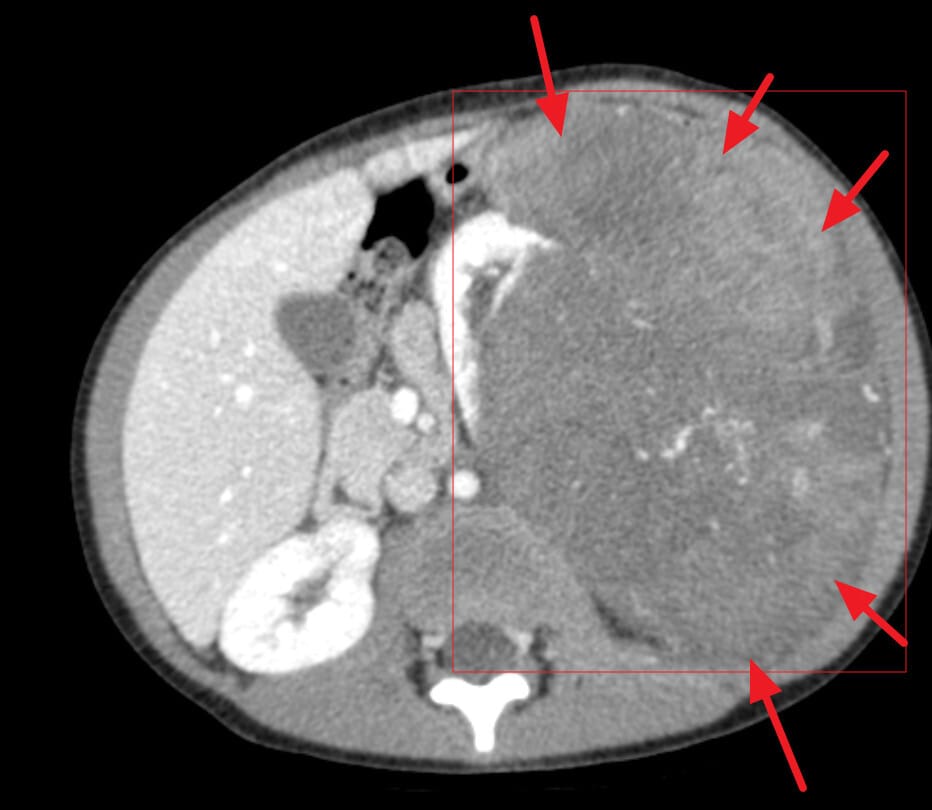

CT 소견

Wilms tumor의 표준 평가 검사로, 종양의 범위, 신장 내 위치, 전이 유무를 평가합니다.

| 🟧 불균일한 고형 종괴 |

| 중앙부 괴사 또는 출혈로 인해 조영증강이 불균일하게 나타납니다. |

| 🟧 Claw sign (발톱 징후) |

| 정상 신장 실질이 종양을 감싸는 모습으로, 종양이 신장에서 기원했음을 시사합니다. 이는 Wilms tumor와 비신장성 종양을 감별하는 데 유용합니다. |

| 🟧 폐 전이 확인 가능 |

| 폐로의 조기 전이를 평가하기 위해 흉부 CT를 함께 시행하며, 작은 결절이 보일 수 있습니다. |

Gaillard F, Wilms tumor. Case study, Radiopaedia.org (Accessed on 24 May 2025) https://doi.org/10.53347/rID-5957